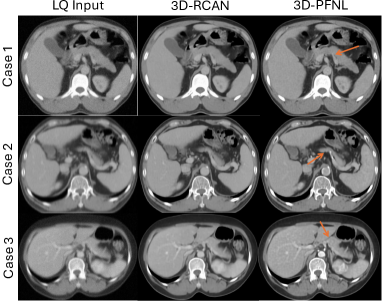

As shown in Table I, both 3D-PFNL and 3D-RCAN models enhanced the quality of the LQ PV CT. There was very little difference ( 1%) between the 3D-PFNL and 3D-RCAN models. As seen in Fig. 2, the proposed 3D-PFNL method recovered sharper edges of the pancreas, whereas the 3D-RCAN model over-smoothed the edges of the pancreas. Of note, the edge reconstruction loss used in the 3D-PFNL model shifted the focus from perceptual quality to structural enhancement. This is in contrast to existing restoration models [25, 17, 18] that are optimized by the reconstruction loss alone. However, an increase in quality does not necessarily mean that it can facilitate downstream tasks, such as segmentation.

However, there was no significant difference in the performance between the two models. This can be attributed to the small number of patients (n = 16) in the test data subset, and it is the major limitation of our work. Another limitation is the introduction of artifacts on the portal venous phase CT. 3D-PFNL attempted to fuse information from the three phases to reconstruct a high-quality PV phase. As shown in case 3 of Fig. 2 and Fig. 4, the contrast of the aorta was enhanced in the portal venous phase, but it is not a feature of this phase. Furthermore, low-quality PV CT was simulated through intensity-based degradations, and the proposed model was trained and evaluated on the same VinDr dataset. The generalizability of the model to external datasets (e.g., low-dose CT) is currently undetermined. In the future, validation of the approach on a larger sample size and with additional organs and structures is necessary.